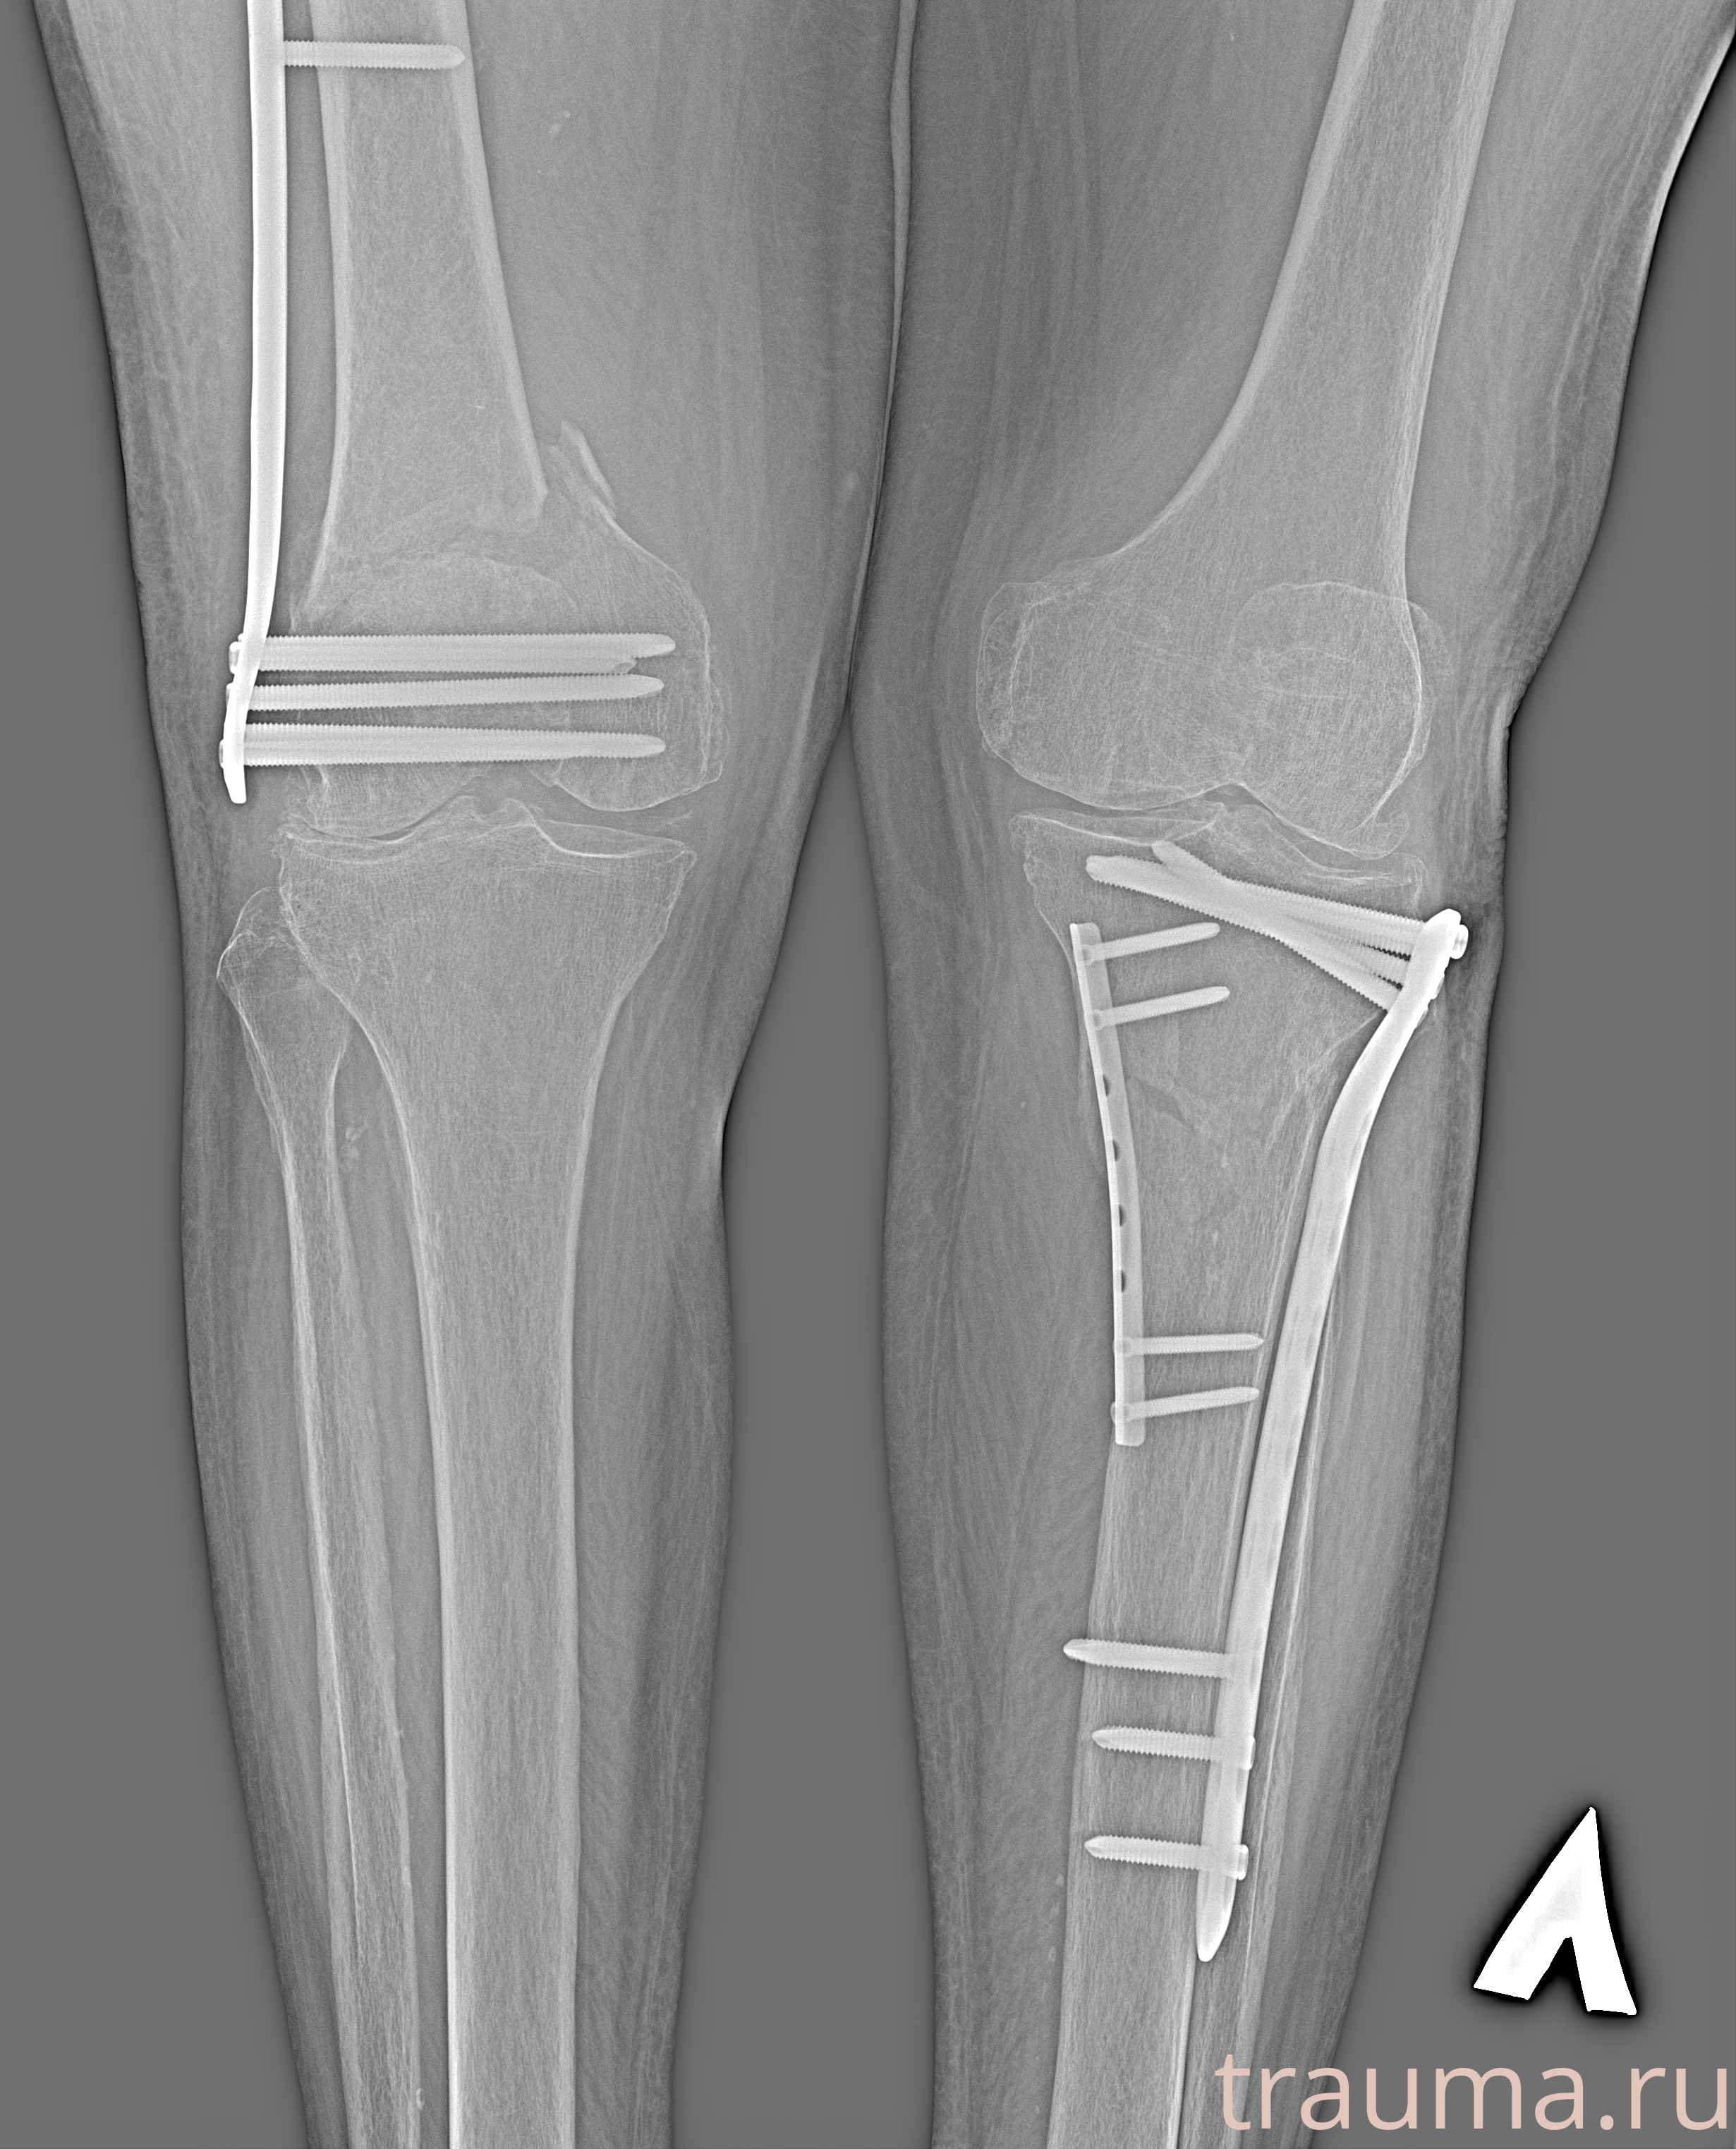

Рентгенограммы

Рентген на дому: по вашему адресу приезжает врач-рентгенолог, травматолог-ортопед с мобильным рентгеновским аппаратом, проводит диагностику травмы или заболевания, делает необходимые рентгенограммы, дает рекомендации по дальнейшему лечению. Получить качественные снимки в домашних условиях возможно благодаря уникальной методике, разработанной МосРентген Центром для института  Склифосовского